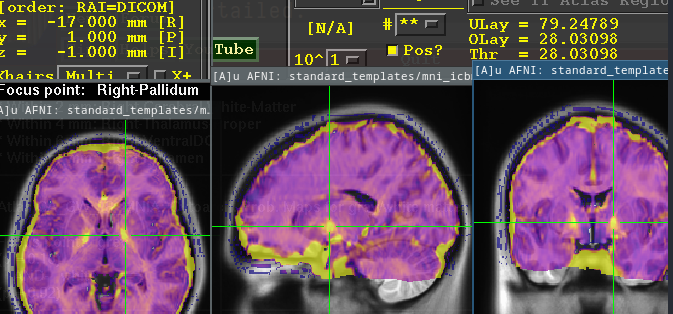

Measure of Tissue Iron concentration.

- see Pallidum ⇒ highest intensity iron signal